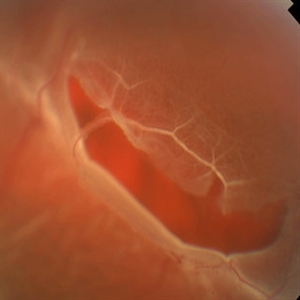

Boat-Shaped Hemorrhage

Mar 1 2014 by Homayoun Tabandeh, MD, FASRS

Boat-shaped hemorrhage in a patient with retro-hyaloid hemorrhage associated with proliferative diabetic retinopathy.

Condition/keywords: diabetic retinopathy